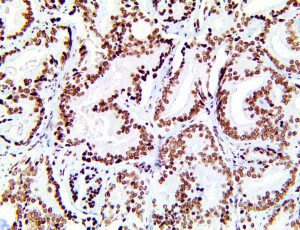

It is the ICU physician who is most likely to witness one of the deadliest manifestations of the abnormal immunological response, the cytokine storm syndrome (CSS). This response is also referred to by some as the cytokine release syndrome (CRS). CSS is characterized by continuous activation and expansion of macrophage and lymphocyte populations, which secrete large amounts of cytokines, causing the cytokine storm. This massive cytokine release is akin to hemophagocytic lymphohistiocytosis (HLH) disease, a syndrome characterized by initial unchecked and persistent activation of cytotoxic T lymphocytes and NK cells.

Clinical and laboratory manifestations of HLH include fever, enlarged liver and/or spleen, neurologic dysfunction, coagulopathy, liver dysfunction, cytopenias (i.e., low levels of erythrocytes, leukocytes, and/or platelets), hypertriglyceridemia, hyperferritinemia, hemophagocytosis, and eventually diminished NK cell activity as the immune system becomes progressively paralyzed. HLH can be familial (primary HLH) or secondary to another disease process (sHLH), such as rheumatic disease, in which it is referred to as macrophage activation syndrome (MAS, characterized by elevated ferritin).